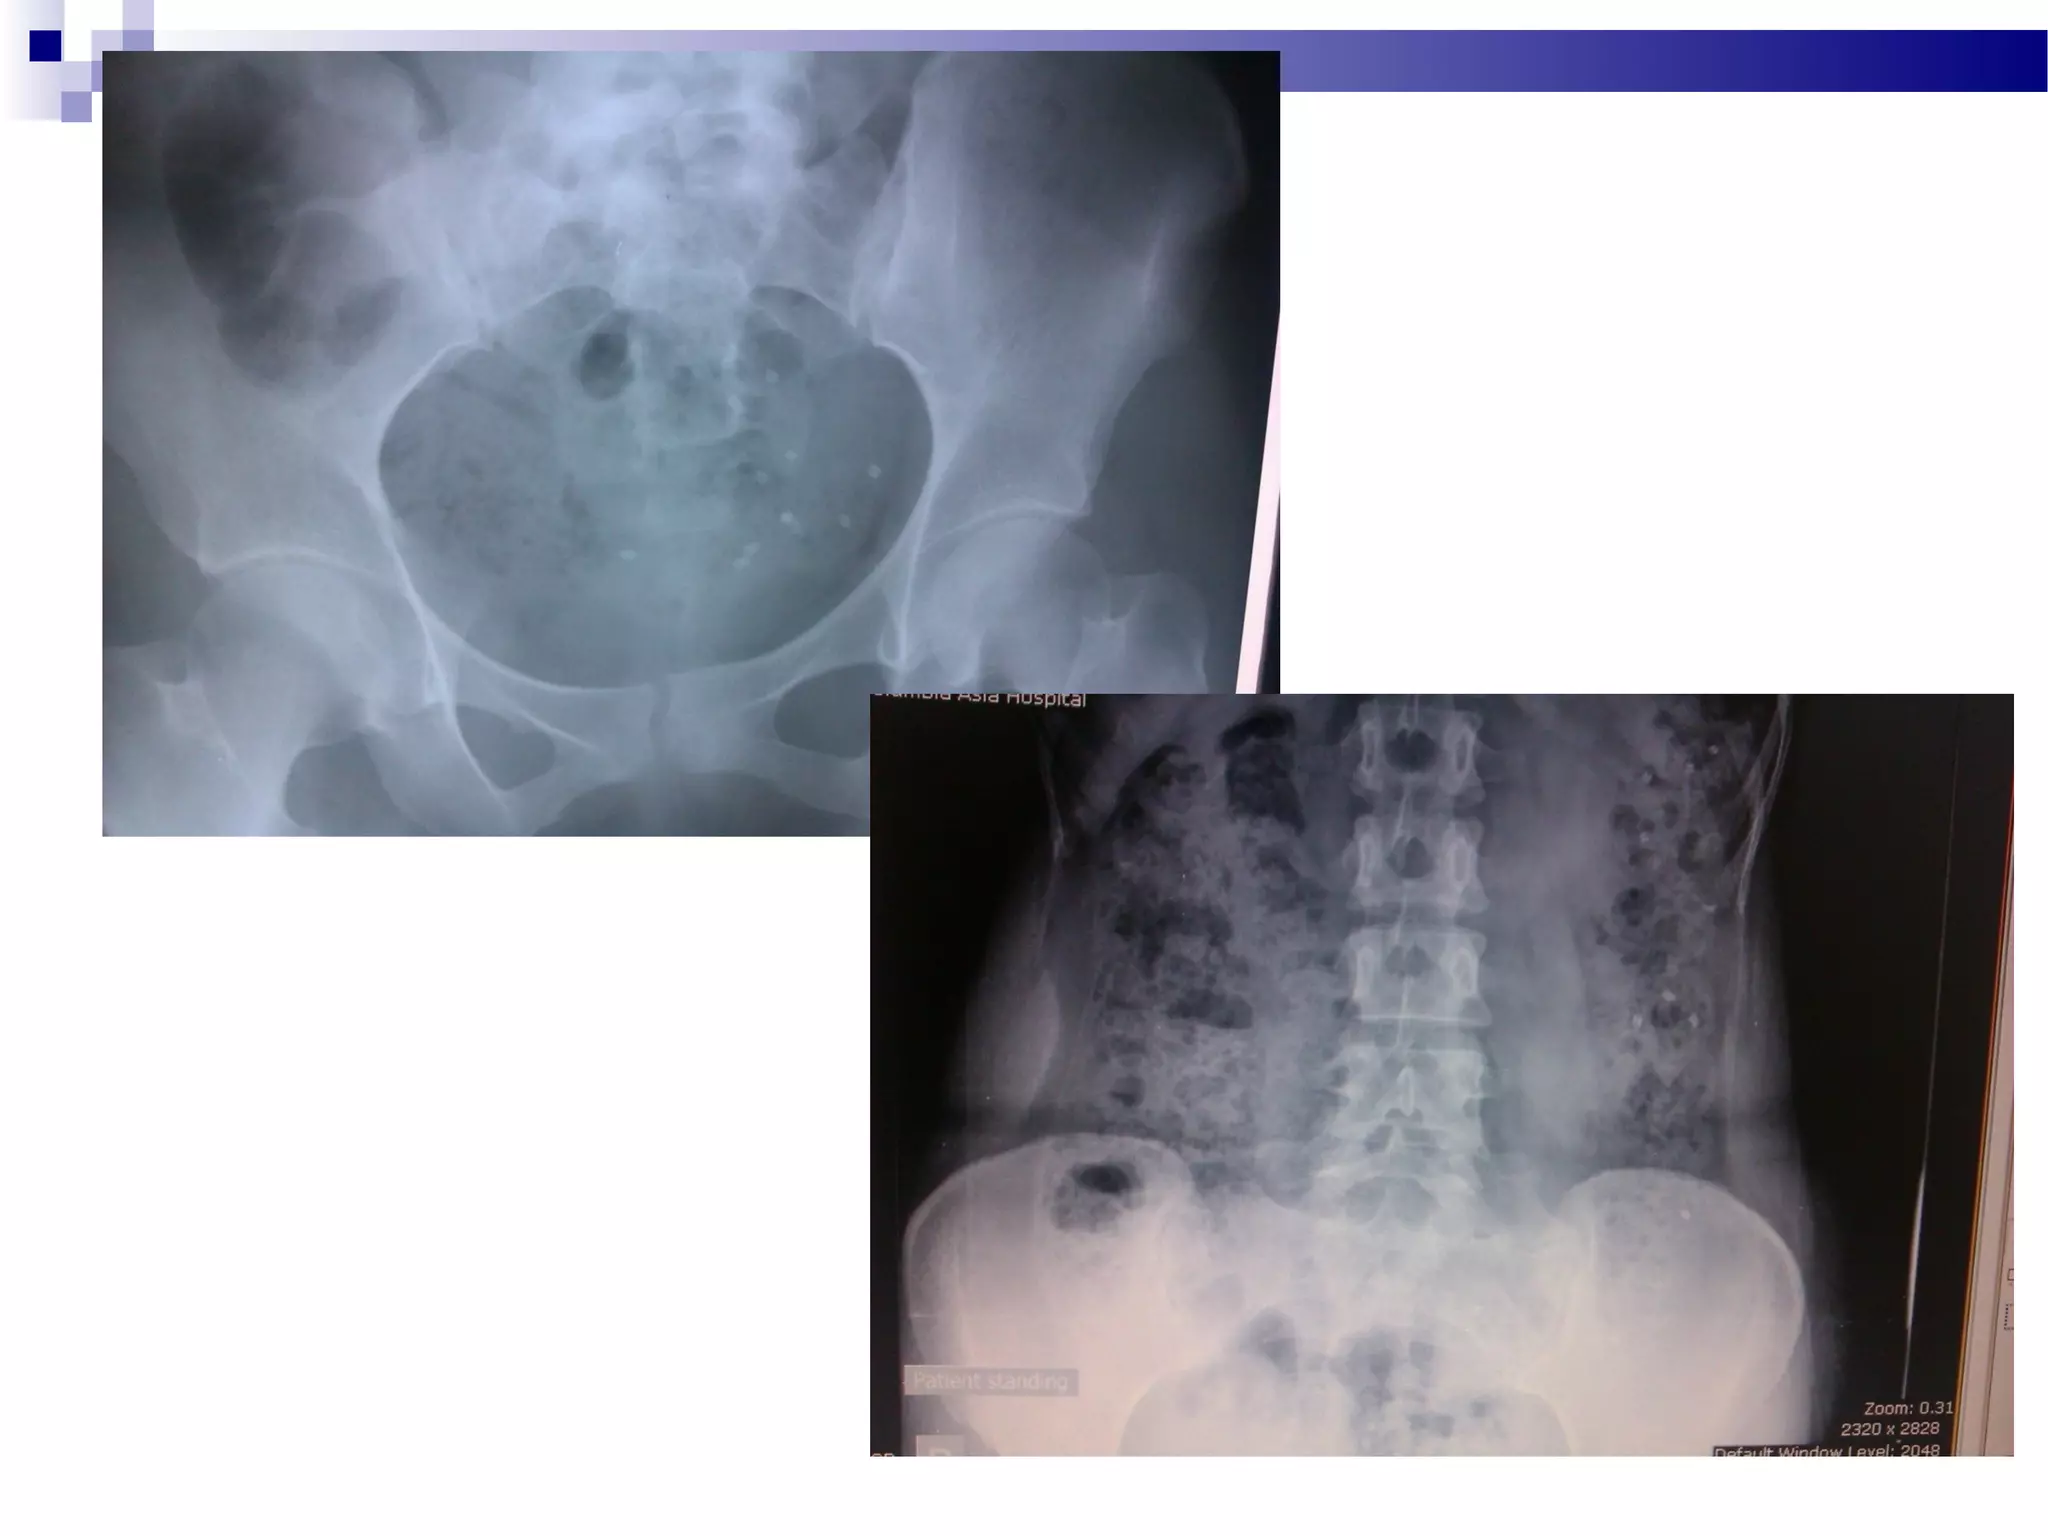

 Transit study

Anorectal manometry, transit study very useful